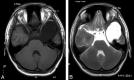

CE-MRC has been in use for the past 15 years and was reported to be a useful method in the evaluation of CSF disorders and hydrocephalus. The use of CE-MRC in conjunction with other MR imaging techniques has been shown to be effective in selected cases for the evaluation of several disorders of cerebrospinal system. CE-MRC has certain advantages over other cisternographic studies with fewer side effects if performed properly. Although intrathecal Gd administration is not widely accepted yet, several recent studies have reported the safety of small-dose intrathecal gadolinium injection. In this review, we describe CE-MRC and review recent applications in several clinical conditions.